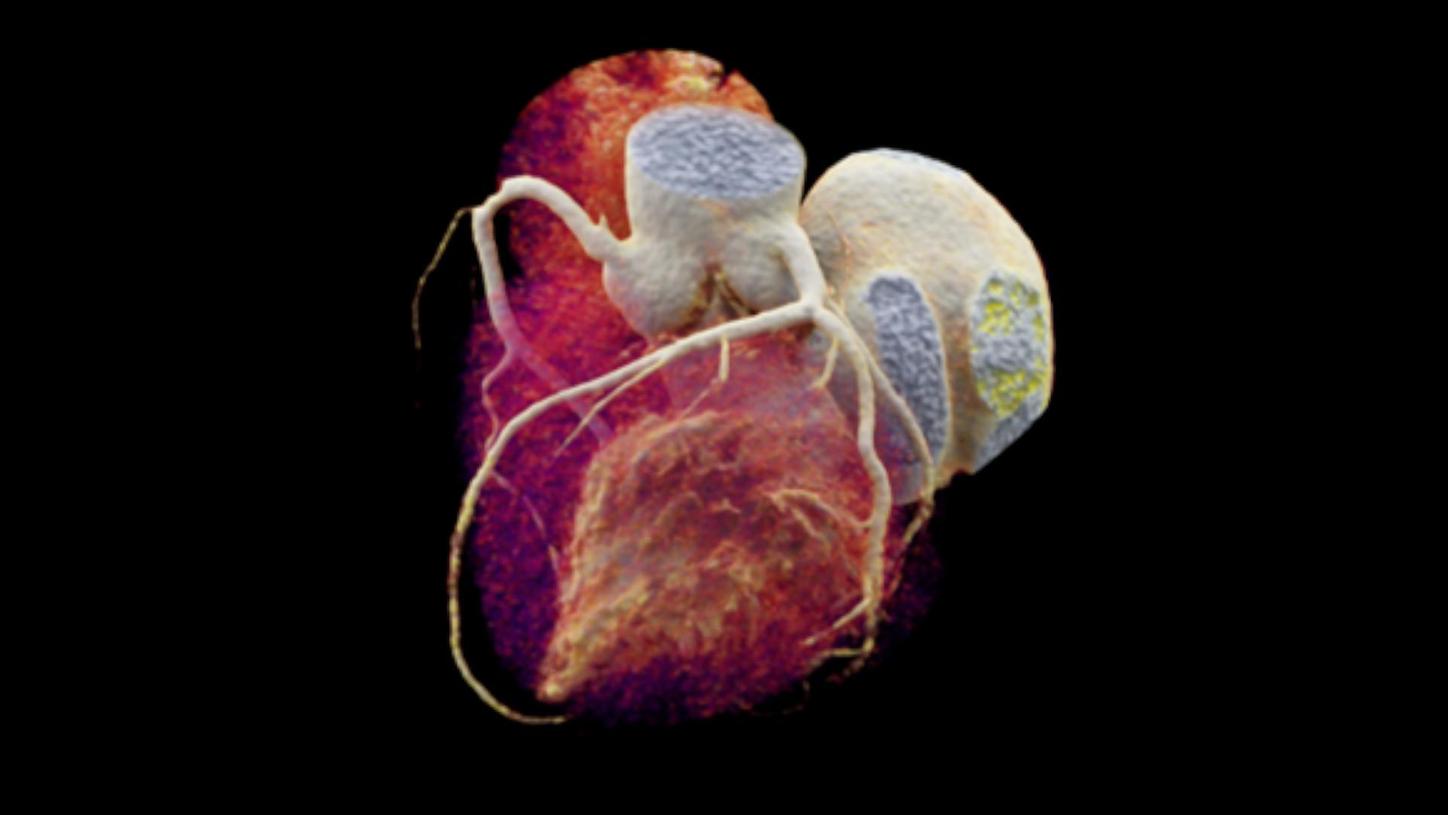

One such case where minimally invasive solutions, including image-guided therapy, were used to improve the treatment process of a patient is Frank’s case. At the request of a friend, Frank, a seemingly healthy middle-aged businessman, went for a cardio checkup at his local hospital. Despite maintaining a healthy diet, regular exercise regime and being a non-smoker, a coronary CT angiogram (CCTA) showed 90% occlusion in Frank’s right coronary artery. Luckily, this form of non-invasive imaging was enough to provide the doctors with the information they needed to successfully treat Frank and quickly get him on the road to recovery.

Already today, we cover many clinical topics and tailor our radiology products and solutions along clinical pathways. With intelligent, digitally connected imaging solutions you can improve diagnostic accuracy, plan treatment options and guide minimally invasive therapy. With our focus towards the world’s major diseases including stroke, coronary artery disease, lung, and liver cancer, we are committed to supporting patients in every step of their journey.